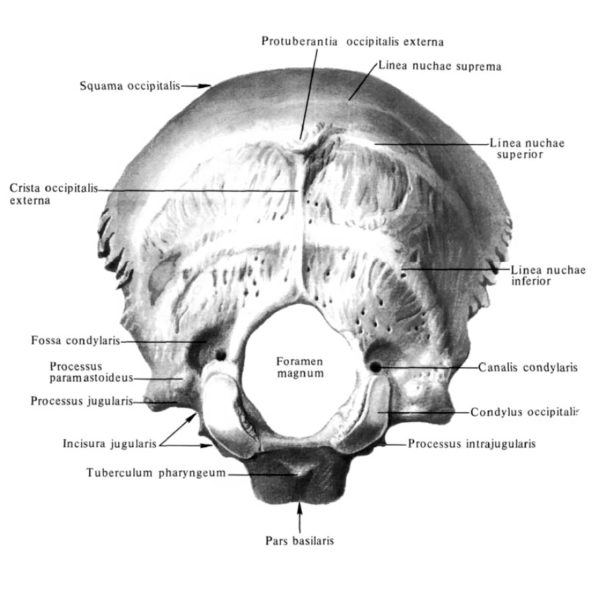

Итого в столбе 24 автономных (не сросшихся) и до десяти сросшихся позвонков, для единой классификации пронумерованные особым образом. Есть, правда, нулевой позвонок, но он – условный. Это черепная кость, расположенная на затылке.